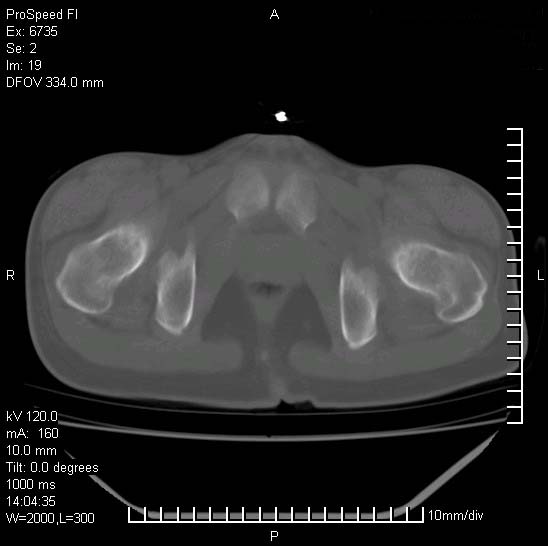

患者自诉胯部疼痛两年余,在当地服用中药,半月前至本院考虑骶髂关节结核,给予抗痨治疗。现发展至右下肢疼痛明显,活动受限,以膝关节处明显,拍膝关节平片无明显异常。

两侧骶骼关节改变,考虑强直性脊炎

左侧骶髂关节面限局性骨破坏,边缘硬化关节腔见钙化物;不出外tb

右侧骶髂关节也有类似改变,只是较左侧轻,首先考虑强直性脊柱炎,不除外结核,建议作hla-b27检查。

典型强脊炎改变,髋关节亦有累及

符合强直性脊柱炎表现。